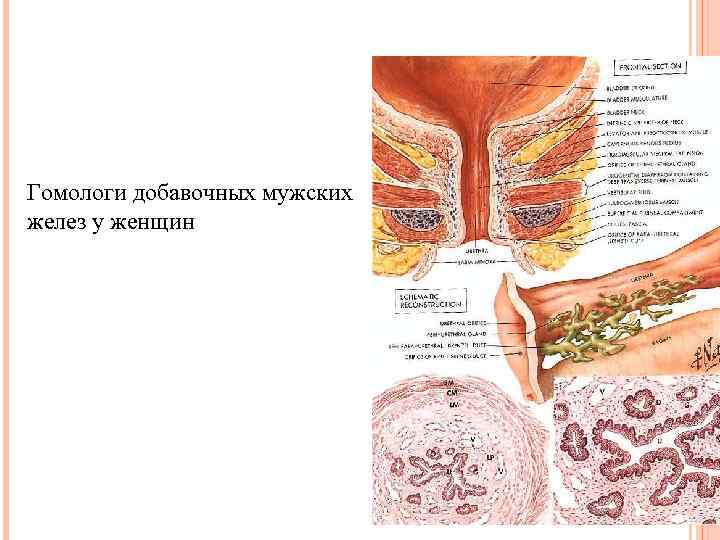

Гомологи добавочных мужских желез у женщин

Гомологи добавочных мужских желез у женщин